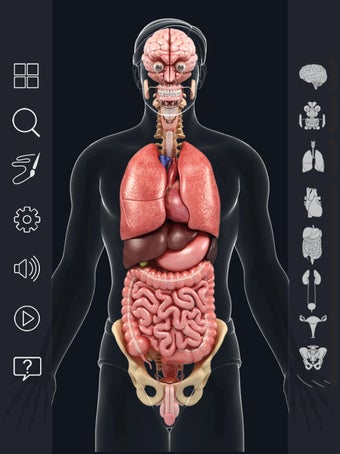

Met deze applicatie kun je 360° draaien rond een zeer realistisch 3D-model van het menselijk lichaam. Je kunt in- en uitzoomen op elk deel om er beter naar te kijken.

De camera kan worden verplaatst om een ander beeld van elk deel te krijgen.

Je kunt alle informatie over de organen krijgen, inclusief hun locatie, hun functie en hoe ze eruitzien.